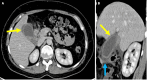

Endoscopic retrograde cholangiopancreatography (ERCP) is a cornerstone procedure for the diagnosis and management of pancreatic and hepatobiliary diseases. Although its diagnostic role has been increasingly supplanted by noninvasive imaging modalities such as magnetic resonance imaging (MRI) and magnetic resonance cholangiopancreatography, the therapeutic applications of ERCP have continued to expand. ERCP is widely used and has a generally favorable safety profile. However, it is important to recognize expected post-procedural imaging findings and serious complications that can arise. The increasing complexity of therapeutic interventions and the growing volume of procedures have led to a higher incidence of complications that often present with overlapping clinical and laboratory features, underscoring the critical role of imaging in differential diagnosis. This review focused on the typical normal ERCP findings and the imaging characteristics of common complications, including pancreatitis, bleeding, ERCP-related infections, perforations, and stent-related complications. Computed tomography (CT) is particularly valuable in timely recognition, management, and surgical decision-making for these complications. Furthermore, MRI offers a radiation-free alternative for managing complications in selected patients. Therefore, radiological modalities, particularly CT and MRI, are critical tools for the rapid diagnosis, management, and surgical decision-making processes for post-ERCP complications.